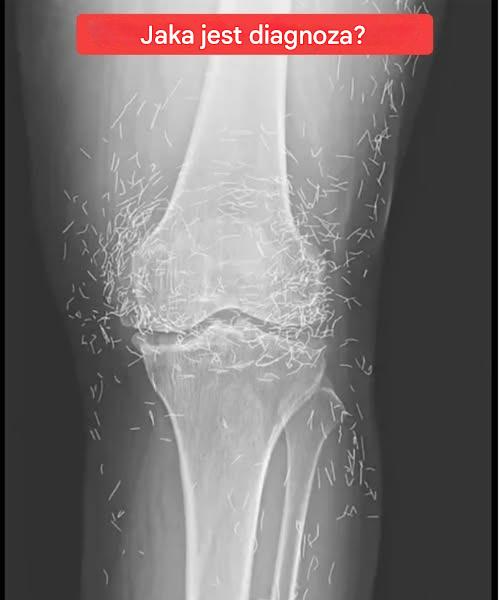

Zdjęcie rentgenowskie ujawnia złote igły do ​​akupunktury w kolanach kobiety – co się naprawdę wydarzyło

Kiedy lekarze zbadali zdjęcie rentgenowskie 65-letniej kobiety z Korei Południowej cierpiącej na silny ból kolana, zauważyli nie tylko objawy choroby zwyrodnieniowej stawów.

Zobaczyli coś nieoczekiwanego: setki drobnych metalowych odłamków wbitych w jej stawy kolanowe.

Ale wbrew popularnym nagłówkom głoszącym „setki złotych igieł” prawda jest bardziej złożona i fascynująca pod względem medycznym.

Przypadek ten, opisany w czasopiśmie Journal of the Korean Medical Science, dotyczył długotrwałego leczenia zwanego akupunkturą ze złota — specjalistycznej formy medycyny alternatywnej stosowanej w niektórych częściach Azji w celu leczenia przewlekłego bólu stawów.

W 2018 roku południowokoreańscy lekarze opublikowali studium przypadku kobiety z zaawansowaną chorobą zwyrodnieniową stawów, która przez 30 lat poddawała się wielokrotnym zabiegom akupunktury złotem.